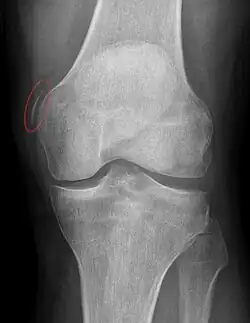

Diagnosis is typically made on radiographs demonstrating the Pellegrini-Stieda syndrome sign accompanied by pain or restriction of range-of-motion of the knee joint.[2] Pellegrini-Stieda syndrome sign is typically described by a longitudinally linear opacity, which is a process that is describes characteristic of calcification in the soft tissue located medial to the medial femoral condyle.[2] This calcification seen on imaging represents the ossification of the medial collateral ligament, which typically does not develop until approximately three weeks after the initial injury.[2]It is important to note to distinguish this radiographic finding from that of a medial femoral condyle avulsion fracture, which is an injury in which a pulling force of a tendon or ligament fractures away a piece of the bone from its attachment site.[2]

Alternative classification syndrome for Pellegrini-Stieda lesions of Type 1 through Type 4 based on their location:[2]

- Type 1- is referred to as a beak-like appearance and describes the ossification arising from the femur and extending inferiorly in the medial collateral ligament.

- Type 2-is defines a tear-drop pattern, localized within the medial collateral ligament without any attachment to the femur.

- Type 3-presents as an elongated ossification superior to the femur lying in the distal adductor magnus tendon.

- Type 4-is also characterized as a beak-like appearance arising from the femur. However, there are some cases where this ossification extends into both the medial collateral ligament and adductor magnus tendon. In then, the original attribution of the syndrome to the medial collateral ligament may now be outdated as many publications have suggested concomitant and even sometimes preferential involvement of the adductor magnus tendon, medial head of the gastrocnemius, or medial patellofemoral ligament.[2]